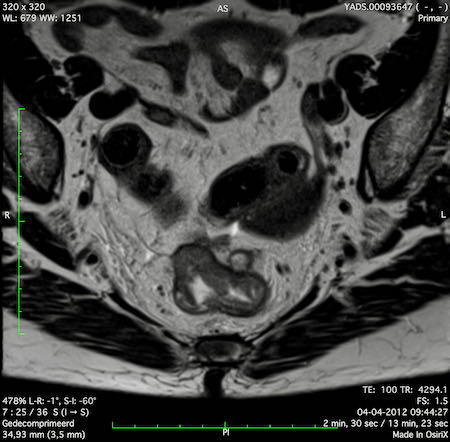

Hình ảnh

Các hình ảnh được cung cấp cho thấy ung thư biểu mô tế bào nhẫn với tình trạng dày lan tỏa thành trực tràng, hình ảnh bia bắn điển hình, và sự xâm lấn mỡ mạc treo trực tràng.